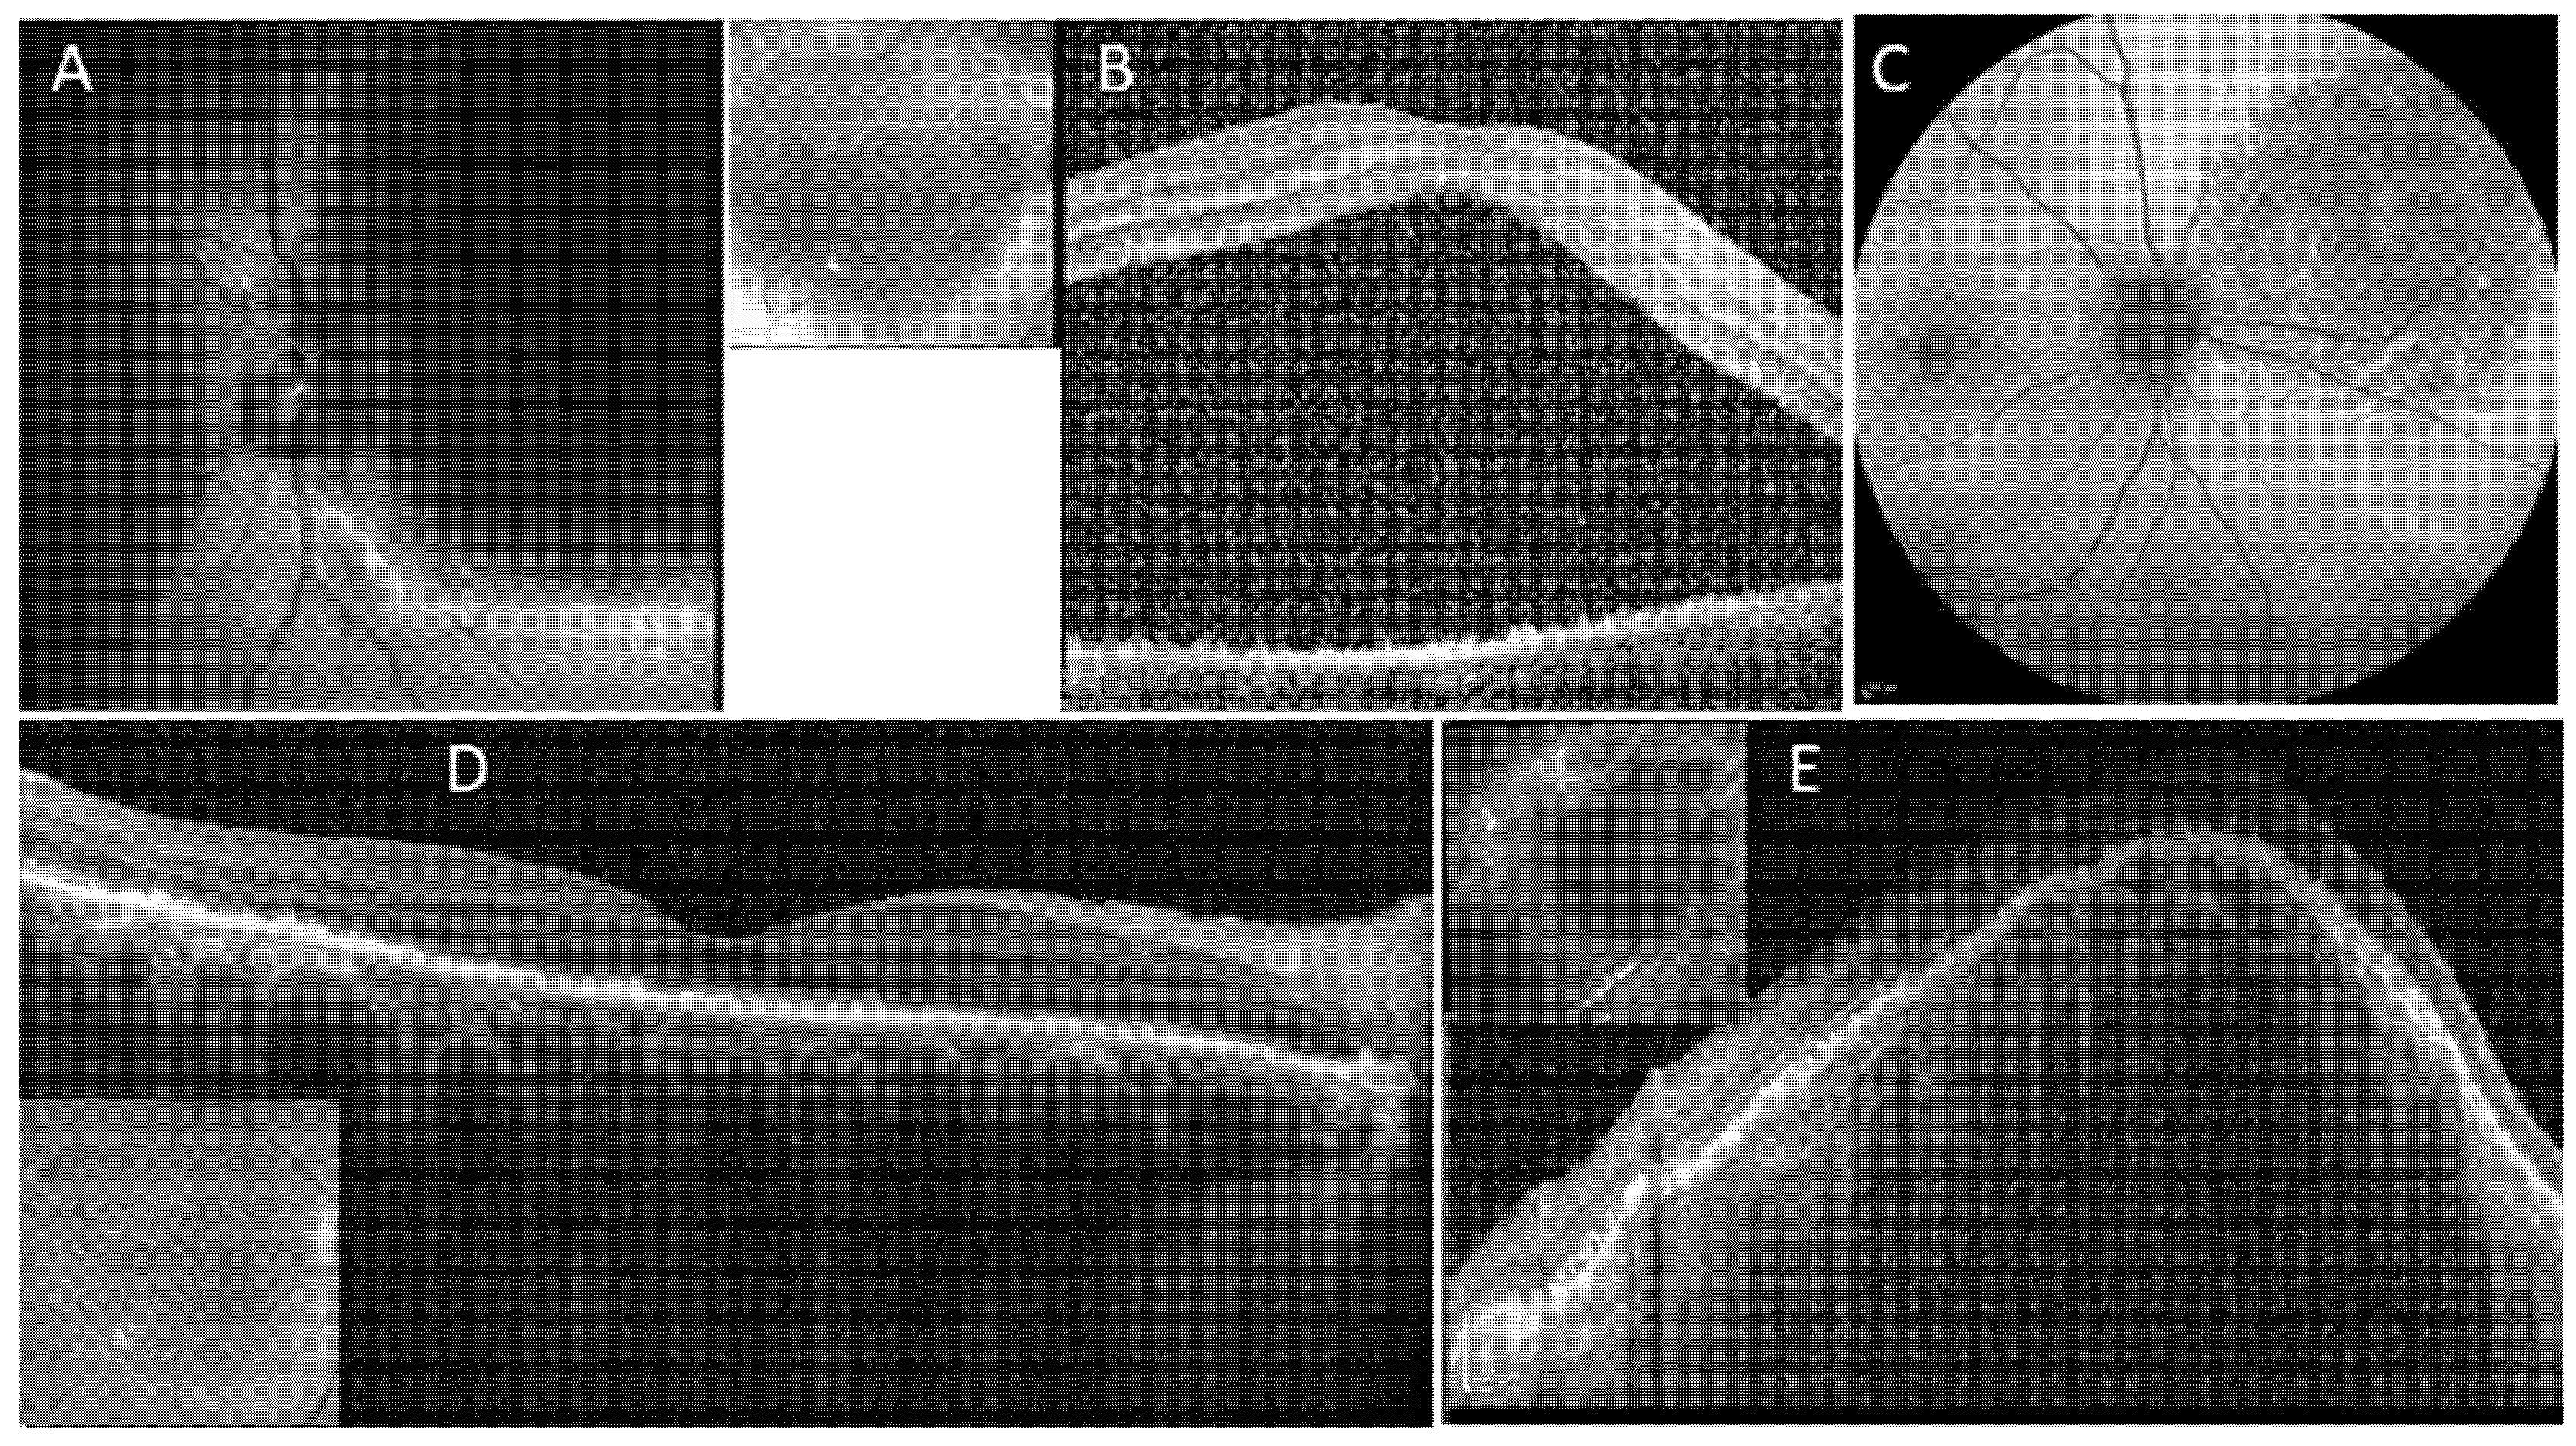

2. Case Number 1